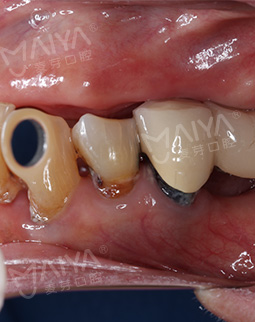

为了确保种植手术的安全性,在种植术前,麦芽口腔宝安机构赵旭峰院长为肖阿姨做了全面检查,考虑到肖阿姨年龄大,又缺牙久,牙槽骨萎缩已经很严重。如果采用传统的种牙方法,不仅需要大量植骨,植骨后还需等待牙槽骨恢复,这将大大增加种植的时间。再三思索后,赵院长决定采用麦芽MAC数字化精确种植技术,这样仅需个别牙齿先植骨,再通过数字化导航技术精确植入植体就可恢复上半口牙齿。"来麦芽口腔果然没有错,年龄这么大,本来还担心能不能种,赵院长给我吃了一颗定心丸。"听完赵院长对方案的讲解后,肖阿姨心头的一块巨石终于落了下来。